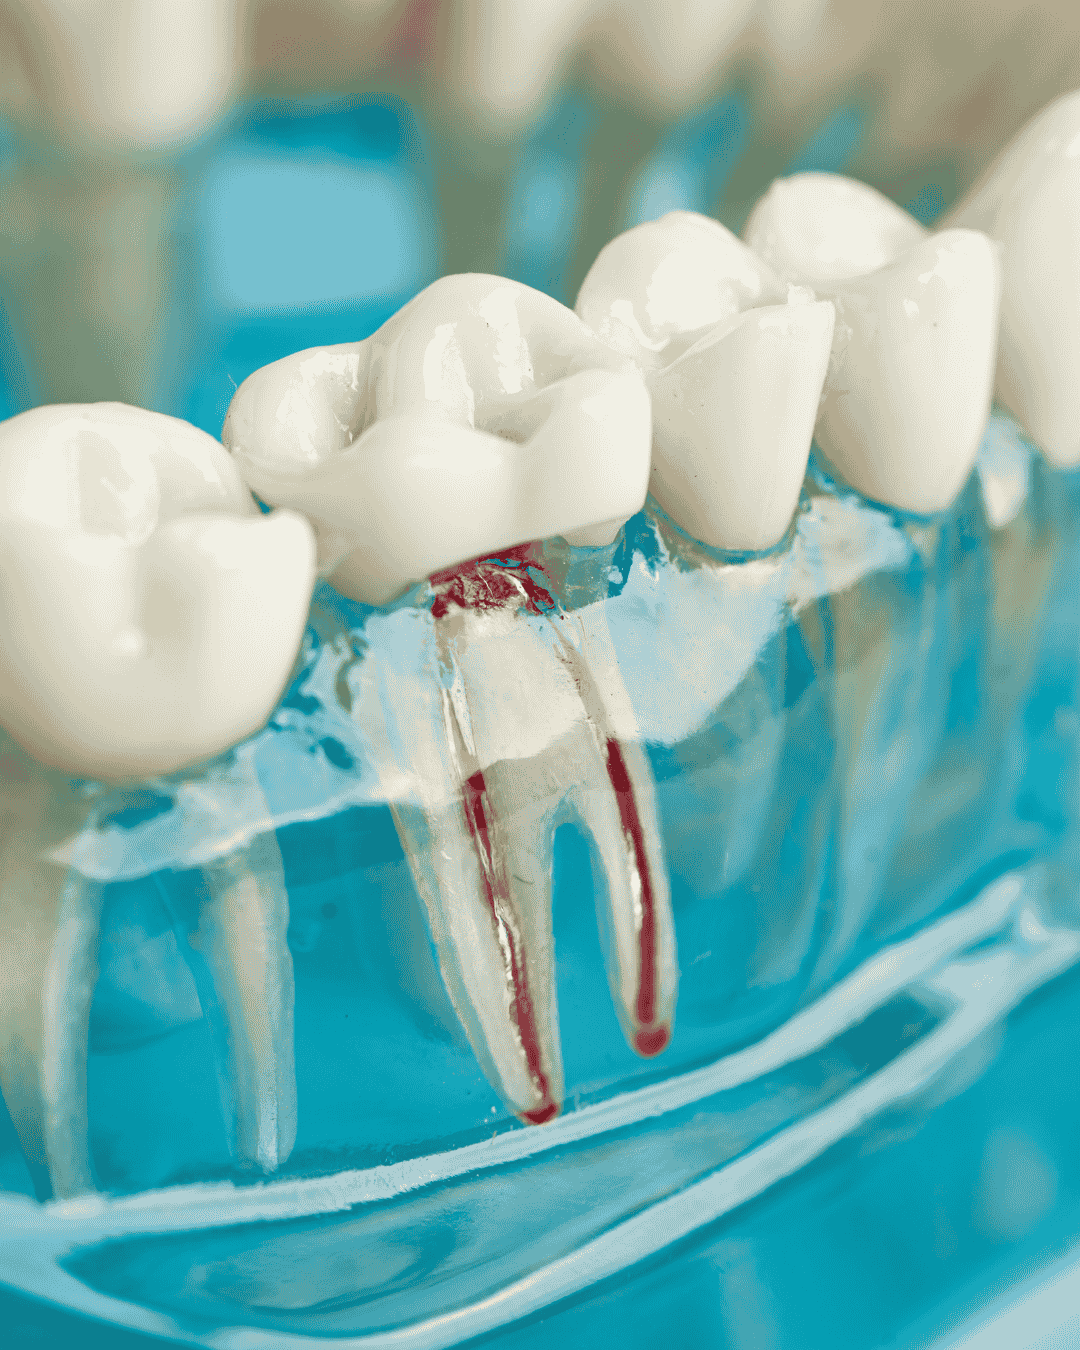

What Is a Root Canal?

A root canal, also known as endodontic therapy, is a dental procedure that removes infected or inflamed pulp from inside the tooth. The pulp contains nerves, blood vessels, and connective tissue that help your tooth develop. When this tissue becomes infected — often due to deep decay, cracks, trauma, or repeated dental work — it can lead to severe pain, swelling, or even abscesses.

Instead of removing the tooth, root canal treatment allows your dentist to eliminate the infection while preserving the tooth structure. Once the pulp is removed, the root canal is disinfected, filled, and sealed to prevent bacteria from entering again. A crown or cap is then placed over the tooth to restore strength and function.